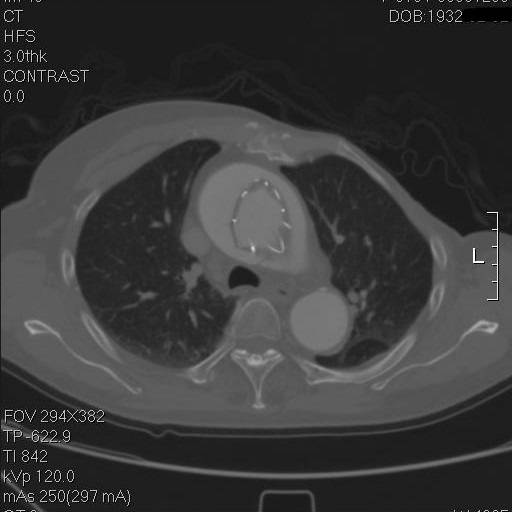

到弓部可以看到,支架远端贴得倒还可以